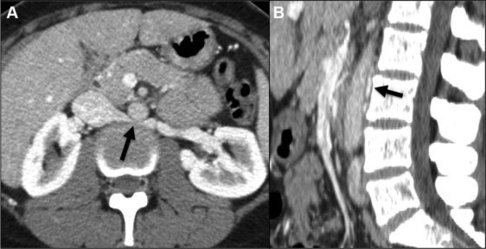

Resim 1,2. Sol böbrek toplardamarı bağırsak atardamarı ve aort'un altında sıkışması

Resim. Tomografide basının gösterilmesi